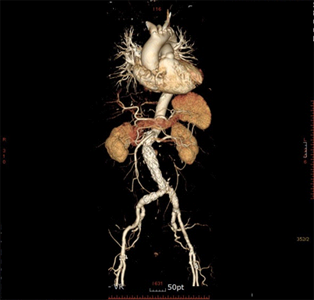

복부 대동맥류

술전 CT 및 복부대동맥 내 스텐트 삽입술 후 CT

술전 CT

복부대동맥 내 스텐트 삽입술 후 CT